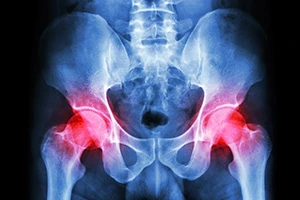

Metal-on-metal hip implants were often used in total hip replacement and hip resurfacing surgeries. These devices were supposed to last longer than other hip implants. Unfortunately, injured patients suffered from various adverse reactions, including:

- Corrosion of the implant

- Metallosis

- Infection

- Severe joint pain

- Implant loosening

- Implant failure